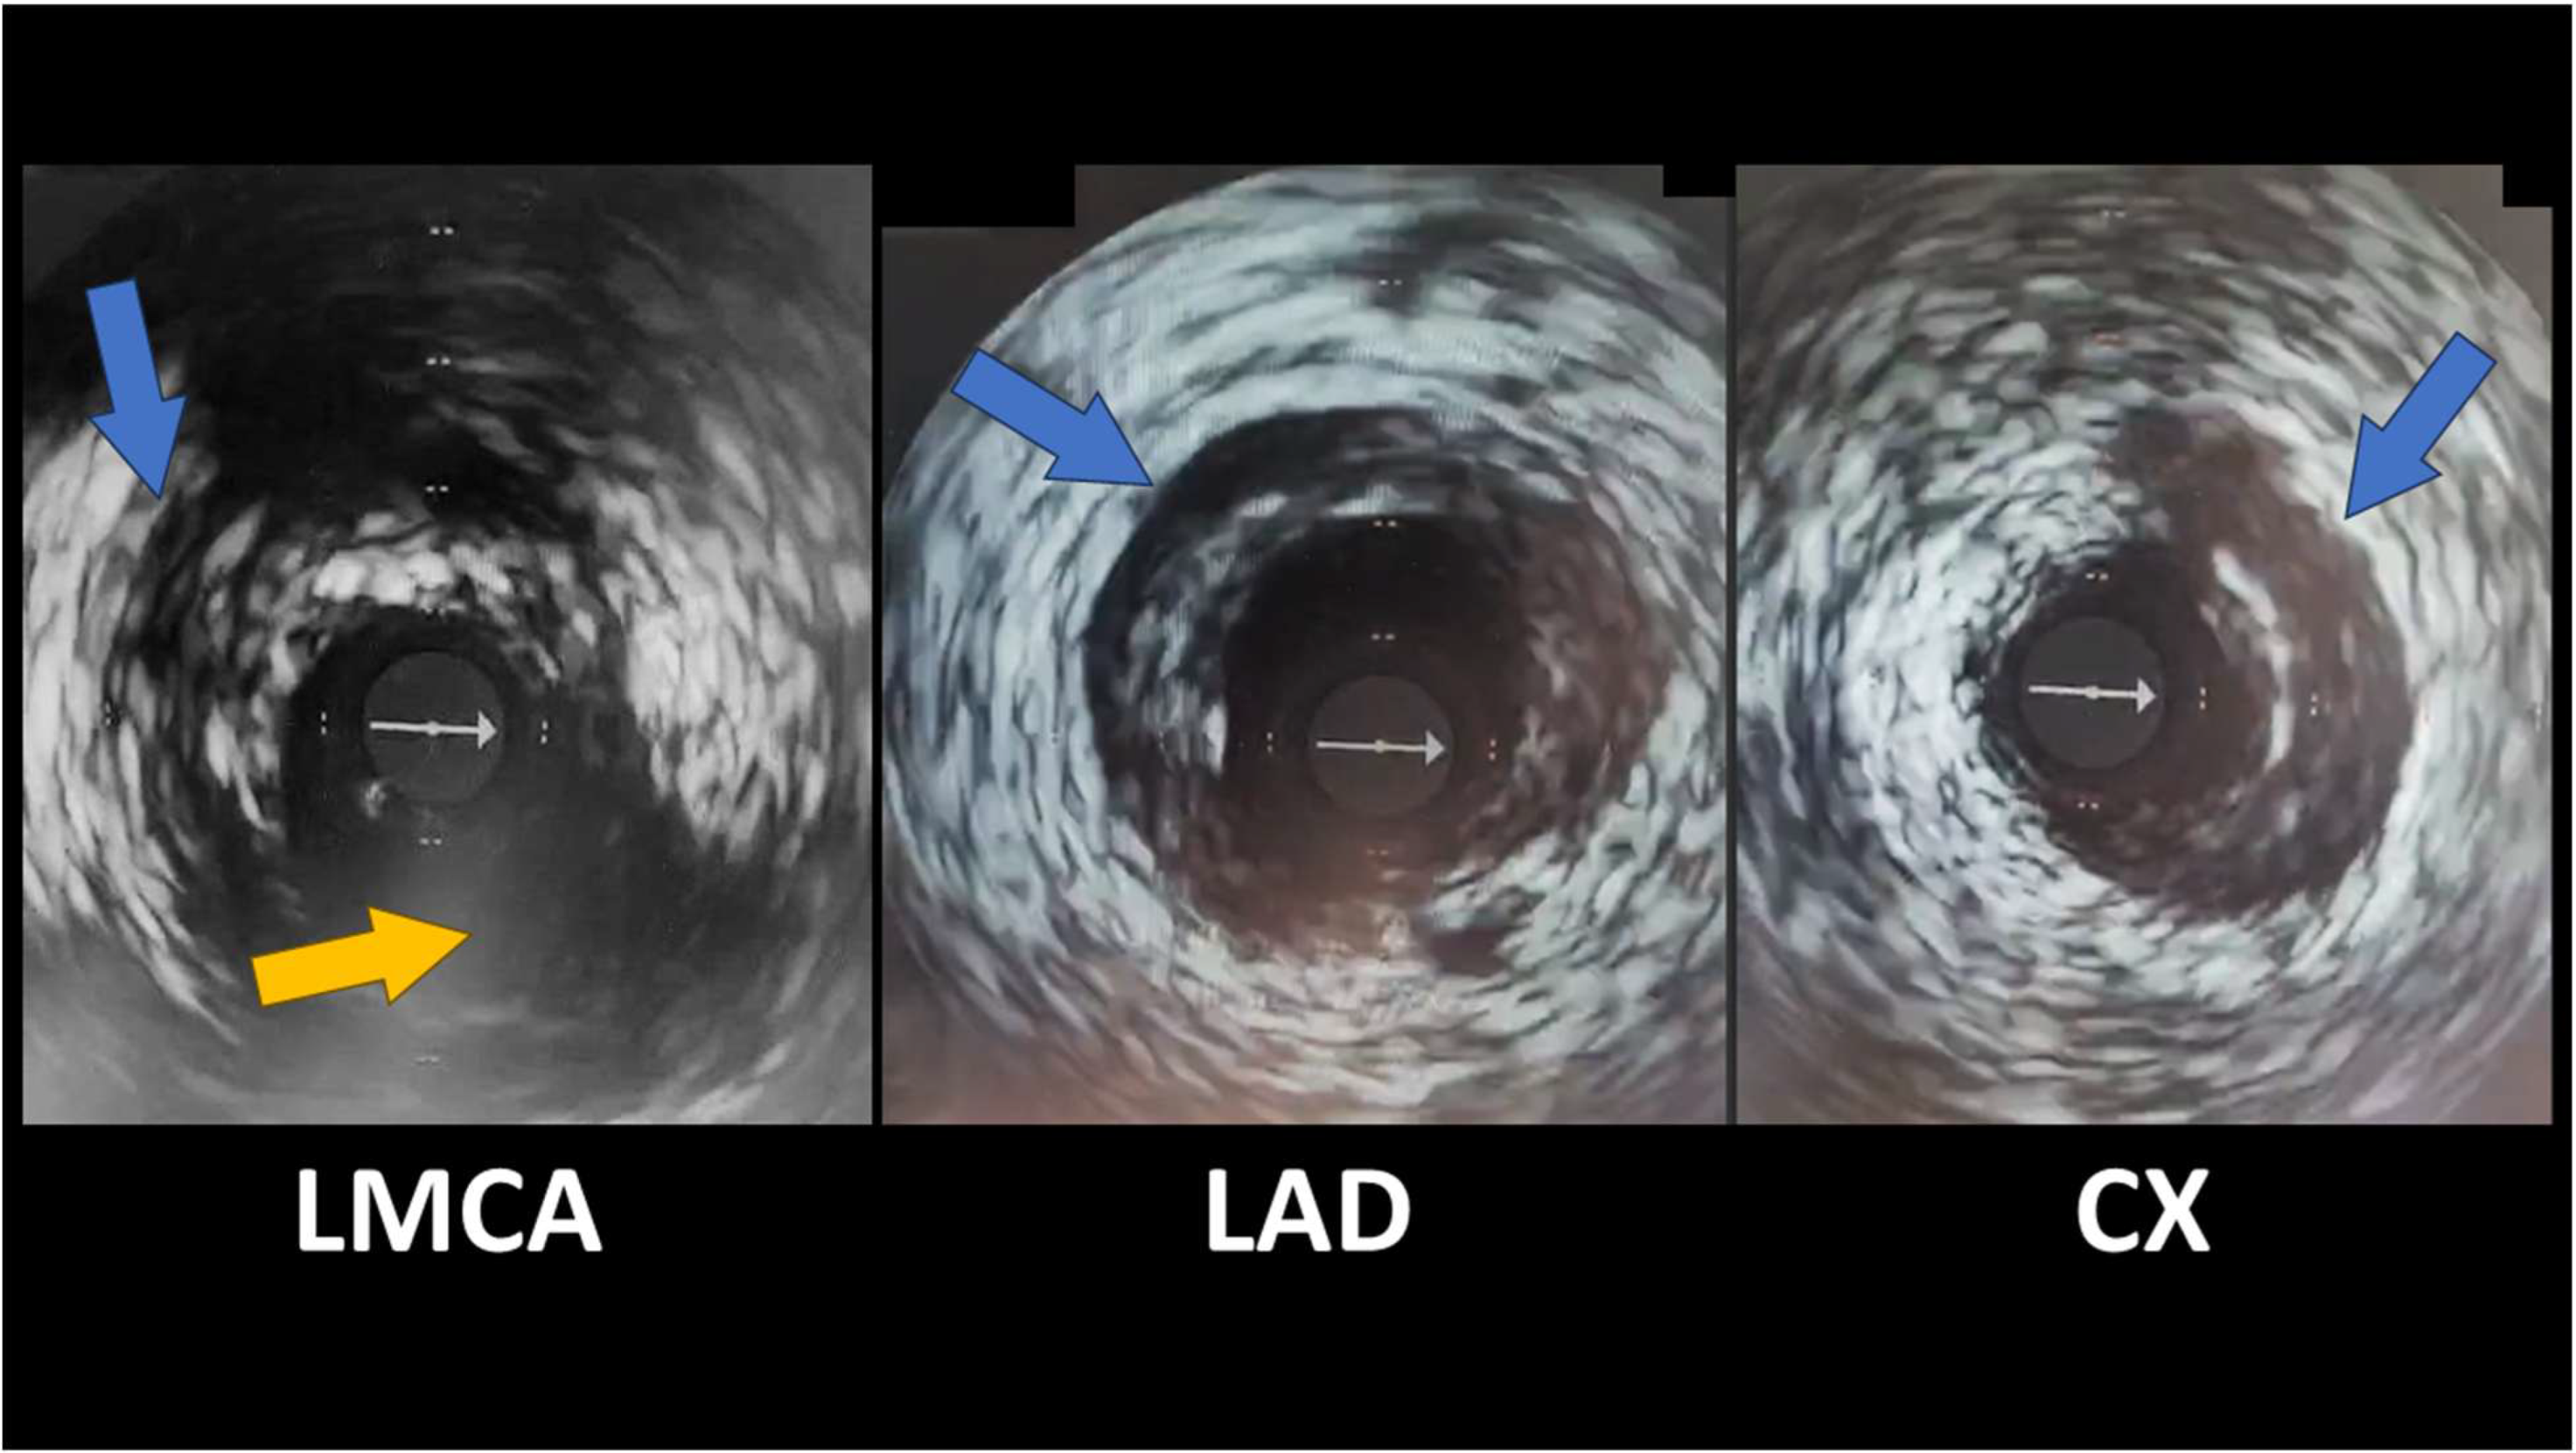

- SCAD Type 3—focal coronary stenosis, usually <20 mm, that mimics an obstructive atherosclerotic lesion on angiography. In reality, these lesions are also caused by an intramural hematoma (of shorter dimensions), but angiographically, they cannot be reliably differentiated from atherosclerotic plaque without additional imaging. Type 3 SCAD is identified in less than 5–10% of cases and usually requires confirmation by additional investigations—intravascular ultrasound (IVUS) or optical coherence tomography (OCT)—to identify wall dissection and exclude atheroma [5,6,33].